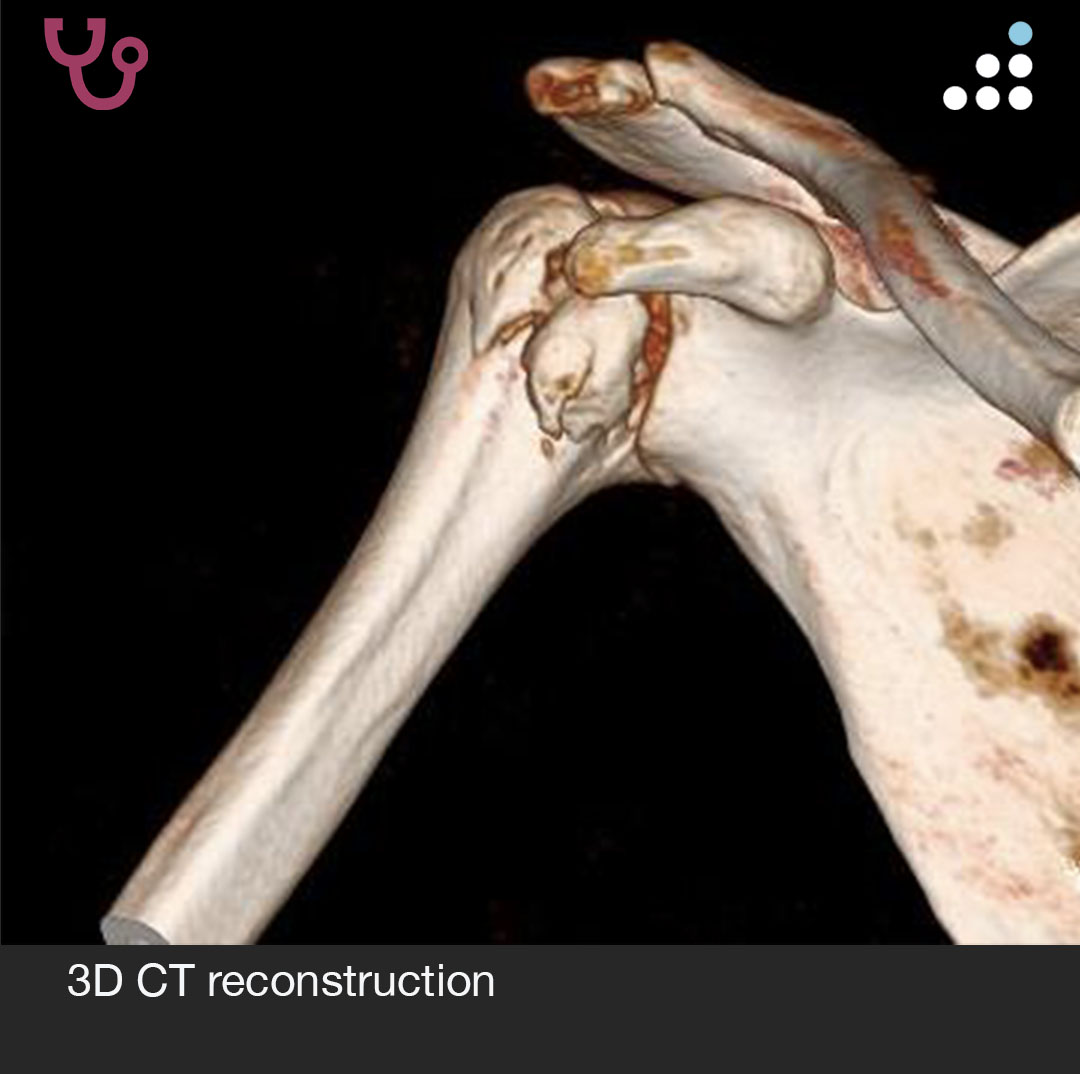

@orthobullets If there is still some cartilage left on the reverse Hill Sachs I’ve had some luck with doing a humeral head osteoplasty. I’ll use allograft chips or cement to backfill the defect after I tamp up articular surface and then try to get everything repaired especially in young pts